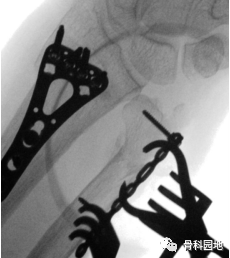

a透视确认后,将钢板完全固定。元旦螺钉不要突出到远端尺桡关节。b进行透视成像以评估完全固定钢板的位置。

尺远端骨折合并桡骨远端骨折患者术前、术中及术后影像。